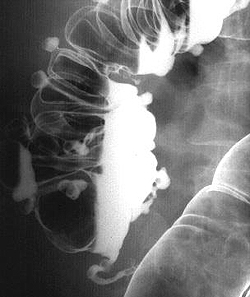

Рентгенографическое исследование толстого кишечника с барием (ирригоскопия) позволяет диагностировать дивертикулит, если невозможно проведение колоноскопии, или она дает неоднозначные результаты. Дивертикулы на рентгенографии определяются в виде образований округлой формы, которые имеют диаметр от 0,5 до 5 см. При дивертикулите на рентгенограмме визуализируются одиночные и множественные выпячивания, а края дивертикулов имеют неровные зазубренные контуры. Если на фоне данного патологического состояния происходит перфорация дивертикула с формированием свища, то при проведении рентгенографии свищ будет визуализироваться в виде контрастирующегося тяжа, который распространяется в направлении других органов.

- Рентгенодиагностика. Пациенты с данным заболеванием требуют проведения ирригографии, желательно с двойным контрастированием. На рентгеновском снимке будут видны выпячивания кишечной стенки, сообщающиеся с полостью кишечника. Следует помнить, что при наличии осложнений дивертикулов кишечника сначала необходимо сделать обзорную рентгенографию органов брюшной полости, убедиться в отсутствии признаков перфорации, и лишь затем назначать ирригографию.

Основным диагностическим методом выявления дивертикулов в толстом кишечнике является колоноскопия. Кроме того, при колоноскопии возможно выявить источник внутреннего кровотечения и исключить другие заболевания толстого кишечника. Ирригоскопия с контрастным веществом позволяет выявить выпячивания кишечной стенки.